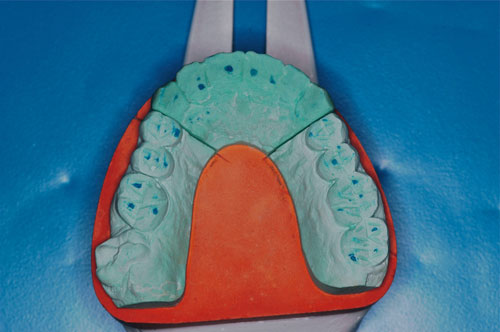

ESTUDIO ESTÁTICO DE LOS MODELOS PREVIOS A LA PRIMERA REHABILITACIÓN APORTADOS POR LA ENFERMA:Modelos Color Blanco

B- ESTUDIO ESTÁTICO DE LOS MODELOS PREVIOS A LA 1ª REHABILITACIÓN APORTADOS POR LA ENFERMA: (La situación oclusal que la enferma tenía antes de que la tocara un dentista (MODELOS COLOR BLANCO)

ESTUDIO ESTÁTICO Y CINEMÁTICO DE LA OCLUSIÓN PRESENTE: Modelos Color Verde

Se realiza un montaje en articulador semi ajustable, mediante la técnica de arco facial convencional para el maxilar superior, y mediante relajación con Laminillas de Long para el inferior. No satisfechos de la certeza del primer montaje, construimos en el un Jig de Lucia que dejamos toda una noche en boca para remontar el inferior al día siguiente a primera hora.